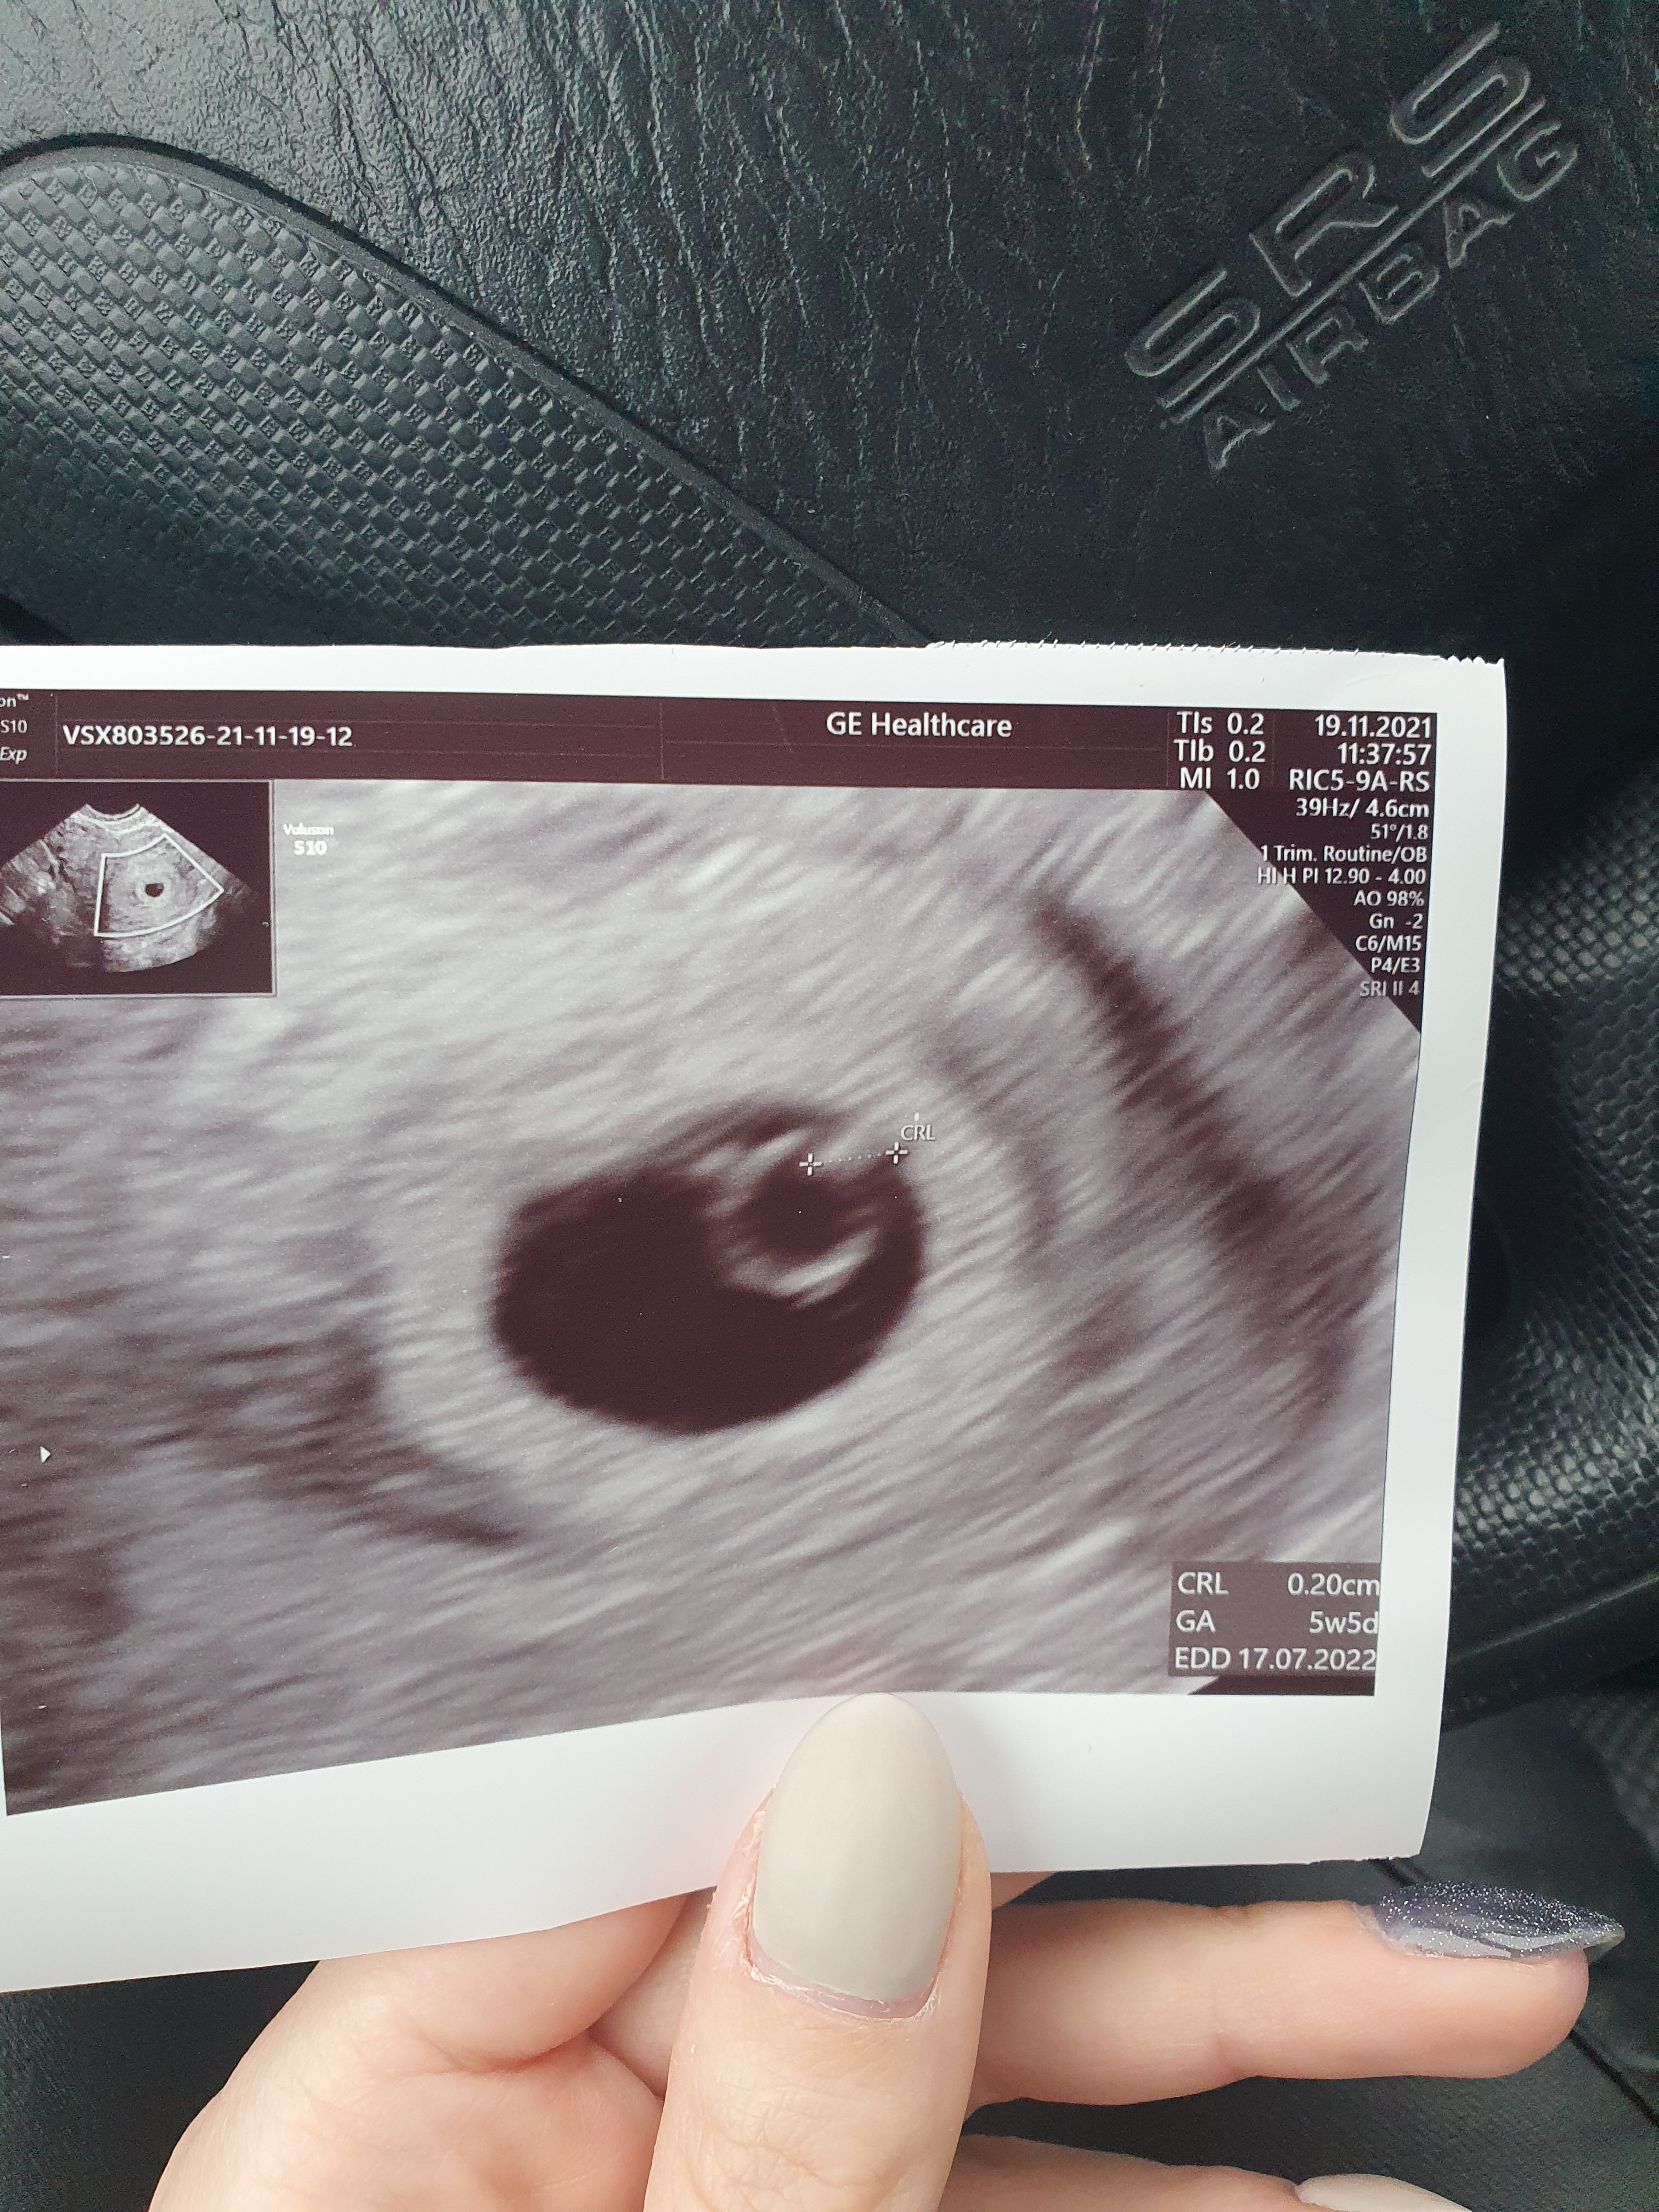

To ja swoje zdjęcie dorzucę z wczorajszej wizyty z OM 6t0d z usg 5t5d

• 20211119_114815.jpg

20211119_114815.jpg

1,9 MB · Wyświetleń: 108